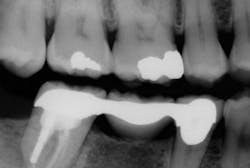

Initially, we evaluate our CBCT scan to give us an understanding of Jane's initial presentation. Similar to panoramic imaging, this "birds-eye" view is critical during the new-patient exam to help us prioritize Jane's treatment needs. Often, clinicians get hung up on "filling the hole." Sirona 3-D imaging provides a roadmap to comprehensive diagnostics. Jane's bridge, despite being asymptomatic, presents with a large periapical radiolucency. We suspect a root fracture from the endodontic post and note that No. 31 has a poor long-term prognosis and is not a candidate for re-treatment.

Our discussion with Jane includes surgical extraction of No. 31 with ridge preservation technique. Once healed, we treatment plan a follow-up CBCT scan, surgical guide, and three endosseous implants at Nos. 30, 31, and the edentulous site, No. 19.

Galileos and CEREC Integration allows perfect case presentation and treatment planning on the first appointment. This creates a problem-solving approach and facilitates proactive treatment in extracting No. 31 with grafting in preparation for implants. Remember, Jane is asymptomatic at No. 31, but with 3-D imaging for diagnostics and treatment presentation purposes, such treatment is readily accepted. After proper management of site No. 31, a new CBCT scan is obtained for evaluation of bone fill and consideration of IA nerve. We recommend guided surgery for precision and enhanced safety. For guided surgery, we simply obtain a full-arch CEREC optical impression. With this data, can prosthetically plan our implant treatment using CEREC software. With SICAT Optiguide Implant Surgical Guide, there is no need for impressions. The digital data allows Sirona and SICAT to fabricate a surgical guide using a pure digital pathway for guided implant dentistry. Once surgical therapy has been provided, the use of CEREC allows for complete control from chairside abutment and restoration fabrication.